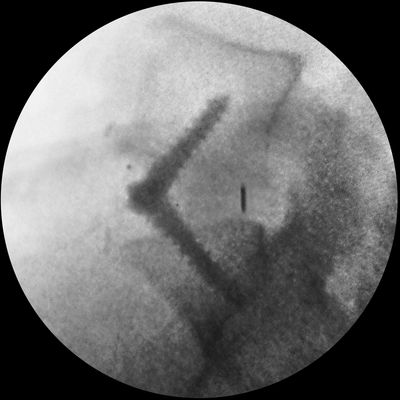

During an anterior lumbar interbody fusion (ALIF), the patient is placed under general anesthesia and positioned on their back. The surgeon makes an incision in the lower abdomen and moves aside the abdominal muscles and organs to access the front of the lumbar spine. The damaged disc is then removed, and the space between the adjacent vertebrae is prepared for a bone graft or an implant, which is placed between the vertebrae. This graft or implant is designed to stimulate bone growth and promote the fusion of the two vertebrae over time.